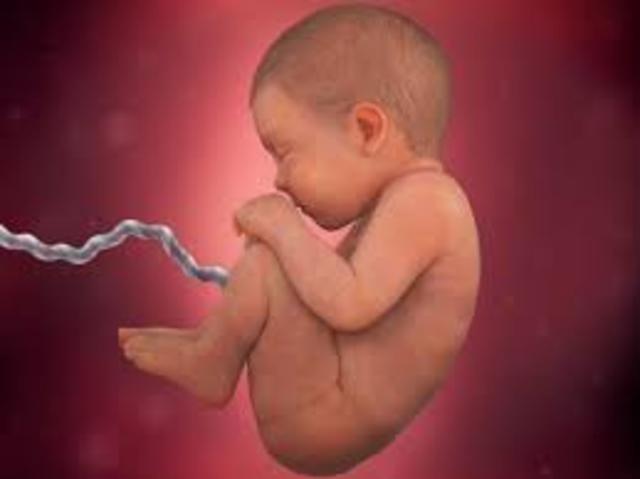

• 8th Month

8th Month

1. The baby gains 2-3 pounds.

2. The baby moves their head into the down position.

3. The baby's lungs are fully developed.